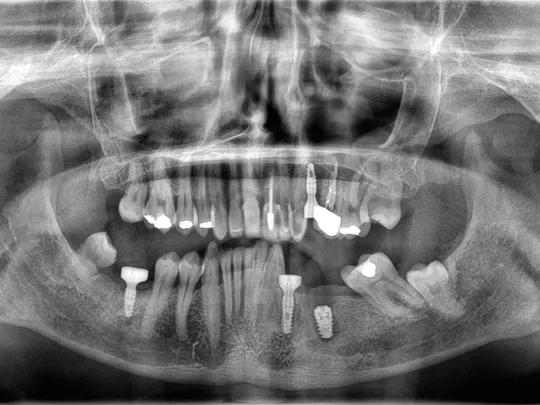

A 64-year-old male patient, in good general health, presented to our clinic with partial edentulism associated with compromised aesthetics, and impaired masticatory function. The patient expressed dissatisfaction with his smile and reported difficulty chewing due to multiple missing teeth.

Clinical and radiographic findings revealed missing teeth, failing prosthetic restorations, and chronic odontogenic infections, collectively contributing to functional impairment which negatively impacted the patient’s self-esteem and overall well-being, leading them to seek comprehensive implant-based rehabilitation. Given the patient’s clinical presentation and functional needs, a digitally driven rehabilitation pathway was selected to leverage the efficiency and predictability of current digital implant ecosystems. Contemporary digital workflows provide improved diagnostic accuracy, streamlined communication, and more predictable restorative outcomes compared with analogue approaches [1]. The integration of virtual planning, CAD/CAM‑guided surgery, and scannable anatomical healing abutments aligns with evidence demonstrating enhanced precision, reduced technique sensitivity, and better intraoral scanning fidelity in implant‑supported rehabilitation. Collectively, these advancements made the digital pathway the most seamless and biologically favourable treatment choice for this case [2].

• Periodontal stabilisation was first carried out to establish a healthy soft‑tissue environment prior to restorative and implant therapy. The esthetic rehabilitation plan included implant placement in sites LR6, LL5, LL6, and UL4, combined with porcelain veneers and crowns from UR3 to UL3 to harmonize the maxillary anterior smile.

• Edentulous sites were scheduled for implant-supported crowns. Axiom X3® Bone Level implants were selected based on their ability to achieve optimal primary stability and prosthetically driven positioning.

9. Panoramic radiograph taken on the day of implant placement.

9